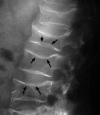

Signs of Nature in Spine Radiology

As medical science developed over time, we have relied on natural imagery to help us recognise and remember things. In this review article, we will be discussing some radiological signs named because of their resemblance to the occurrences in the natural world.